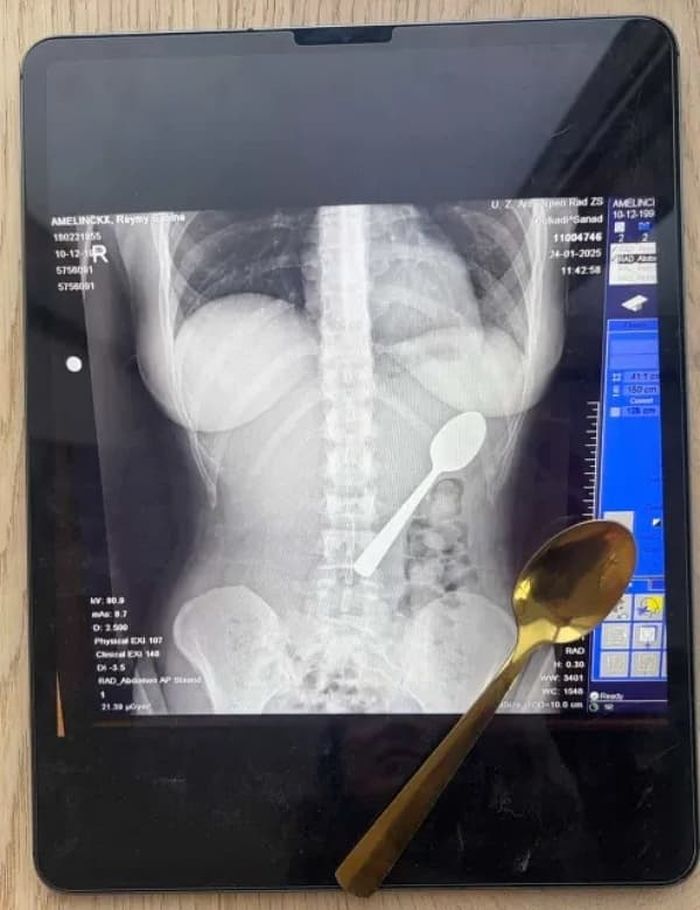

인터넷을 검색해본 레이미 씨는 상황이 매우 심각하다는 것을 깨닫고 급히 응급실로 향했습니다. 엑스레이를 찍어보니 정말로 기다란 숟가락이 그녀의 위장에 떡하니 자리 잡고 있었죠.

의사들은 숟가락이 너무 커서 자연적으로 배출될 수 없다고 진단했습니다. 이틀 동안 수술을 기다리는 내내 그녀는 갈비뼈 사이로 숟가락이 부딪히는 소름 돋는 느낌을 참아야 했습니다.

다행히 위를 절개하는 큰 수술 대신 내시경을 통해 숟가락을 꺼내는데 성공했습니다. 내시경 과정에서 약간의 출혈이 있었고 식도가 상해 며칠간 고생했지만 다행히 영구적인 손상은 없었는데요.